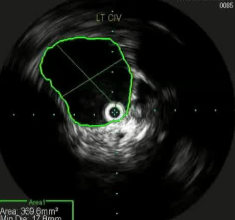

![]() if you look hard enough,如果你的眼睛睁的足够大,你就不难发现,通常下肢血栓清除后是潜在的静脉狭窄 术前的影像检查能为您提供一些线索:可能存在动脉受压的情况;或者淋巴结或其他肿块压迫了静脉。 血栓的上限通常标志着狭窄的部位。 术中血管内超声检查是最准确的。

其它考虑怎么做?How to do IT? 1. 建议将静脉段的扩张程度控制在与所选支架直径相匹配的范围内。【Rahmani 2023 Gibson 2022 Cirse SOP 2014 Raju 2013】 狭窄血管的过度扩张通常不会导致破裂,即便在慢性闭塞的情况下,血管也能承受较大的球囊扩张,并在随后置入较大的支架而不会发生破裂。 只有在以下情况才需例外处理:即在腹膜后区域或鞘管 环绕外科手术已经打开的静脉【joyce DP 2024】 对于慢性静脉阻塞的情况,采用逐渐增大直径的球囊进行多次扩张操作可能并非必要。 除非您无法将 14/16 毫米的气囊顺利穿过病变部位,否则可能需要进行多次扩张操作。【Barbati 2014】 2. 此外,该操作应贯穿整个病变部位的整个长度进行。【Oropailo 2023 Lichtenberg 2018】 ![]() 3. 使用高压球囊【Oropallo A 2023 Gibson 2022】 44岁 男 2次左髂股静脉血栓形成,以下静脉造影